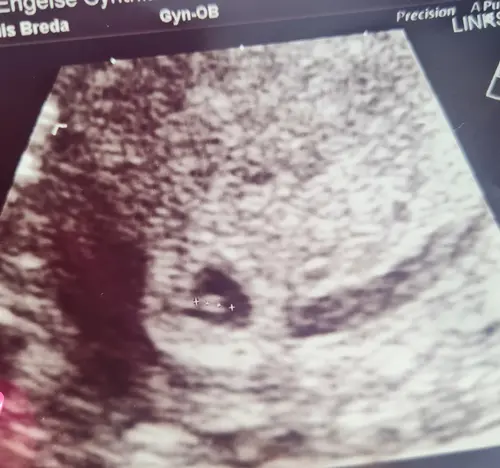

Ik heb mijne al gehad afgelopen woensdag! Was meer omdat ze de dagen daarvoor niks zagen en dus dachten bbz.

We zagen zelfs al een knipperlichtje ❤️ woensdag de volgende echo.